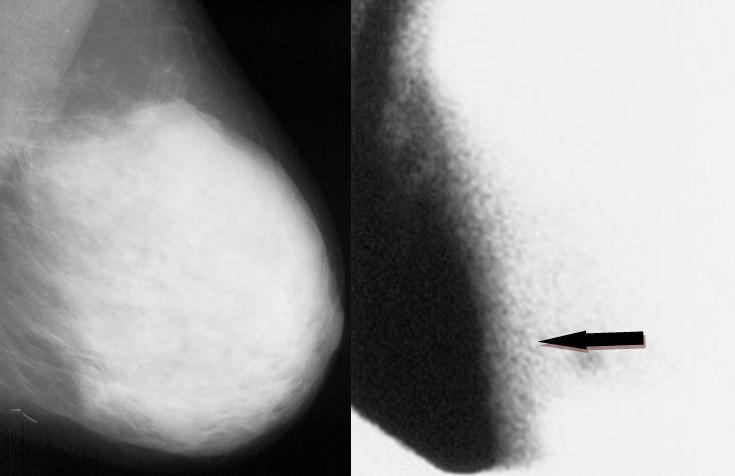

Diagnosticul cancerului la pacientele tinere ridică mari dificultăţi, deoarece mamografia, considerată „standardul de aur” în detecţia cancerului de sân, este mult mai puţin eficientă, ajungând de la o sensibilitate de circa 98% la femeile la menopauză la circa 48% la femeile cu sâni denşi, cu vârsta până în 45-50 ani. Alte metode de diagnostic imagistic utilizate sunt ecografia mamară şi IRM mamar (cu limitările lor în evaluarea unui sân dens), scintimamografia şi, de câţiva ani, PET–CT.

1. Ţesut mamar dens, care determină examen mamografic neconcludent;